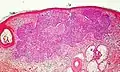

Squamous-cell carcinoma of the skin | Squamous-cell carcinoma of the skin is generally distinguishable by for example relatively more cytoplasm, horn cyst formation and absence of palisading and cleft formations. Yet, a high prevalence means a relatively high incidence of borderline cases, such as basal-cell carcinoma with squamous cell metaplasia (H&E stain at left in image). BerEP4 staining helps in such cases, staining only basal-cell carcinoma cells (right in image). | ![]() |